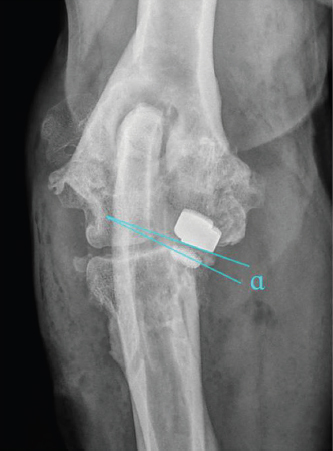

Parallelism of the implants contact surface in the coronal plane was measured on the CrCd view. First, a line parallel to the surface of the HImpl and a second line identical with the longitudinal axis of the elliptically projected metallic base of the UImpl were drawn. The angle between those two lines is reported as medial or lateral opening angle, depending on whether the angle was open towards the medial or lateral aspect of the joint (Fig. 2).

Fig. 2. Determination of implant parallelism showing a medial opening angle α=7°. First-line lies parallel to the surface of the HImpl and a second line is identical with the longitudinal axis of the elliptically projected metallic base of the UImpl.

The median deviation from true humero-ulnar implant parallelism was 10.8° (IQ: 5.5°–17.0°). In only three cases were the desired parallelism of ±1° achieved. In 41 cases, a median medial opening angle of 14.0° (IQ: 8.3°–18.0°) was found with the remaining cases having a median lateral opening angle of 3.0° (IQ: 1.8°–4.6°). The mean medio-lateral position of the HImpl was centered along the width of the humeral trochlear (50.9%; SD: 10.1%).